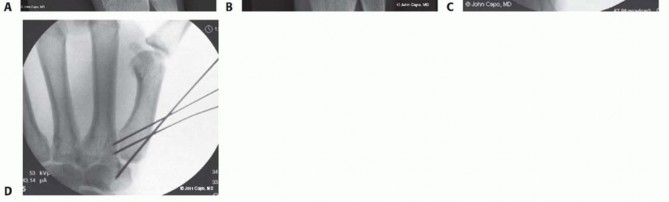

Closed Reduction and Percutaneous Pinning (CRPP)

CRPP is the treatment of choice for classic Bennett fractures where the volar-ulnar fragment is too small to reliably accept a lag screw, yet the joint can be anatomically reduced closed. The reduction maneuver is highly specific, designed to counteract the deforming forces of the APL and Adductor Pollicis. Longitudinal traction is applied to the thumb, followed by palmar abduction and pronation. Direct pressure is then applied to the dorsal-radial aspect of the metacarpal base, effectively pushing the shaft back into the anatomic cradle of the intact volar-ulnar fragment.

Once anatomic reduction is confirmed via multi-planar fluoroscopy, percutaneous fixation is achieved. Typically, two 0.045-inch or 0.062-inch Kirschner wires are utilized. The first wire is driven from the dorsal-radial aspect of the metacarpal shaft directly into the trapezium, effectively neutralizing the proximal pull of the APL. A second wire is often placed transversely from the first metacarpal shaft into the second metacarpal to control rotation and maintain the web space. Pins are cut outside the skin and capped to facilitate easy removal in the clinic.

Image